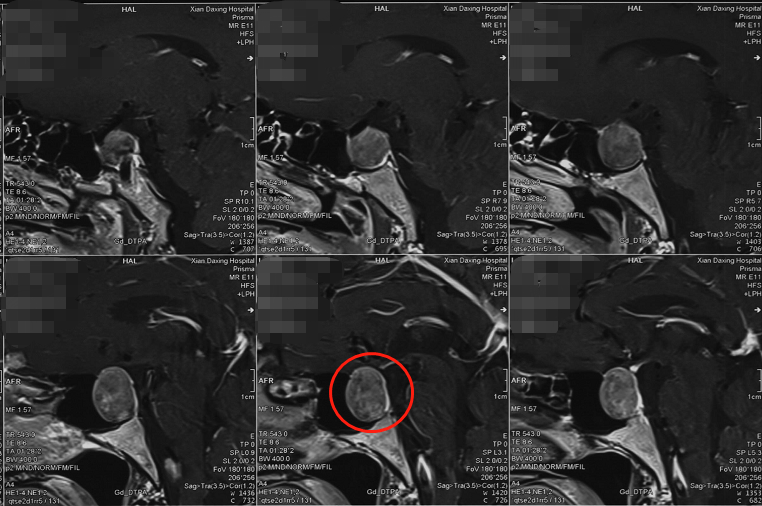

术前影像学检查

“手术切除垂体瘤 , 解除对视交叉的压迫 , 视力才有可能恢复正常 。 当压迫时间较短 , 手术解除压迫后 , 视力可以得到不同程度的恢复;但如果错失手术时机 , 压迫时间过久 , 视力恢复情况可能就不乐观了 。 就目前刘先生的情况而言 , 增大的肿瘤已经严重压迫到视神经 , 视神经缺血时间太长将造成视力的永久性损害 , 必须尽快手术才有挽救视力的机会 。 ”